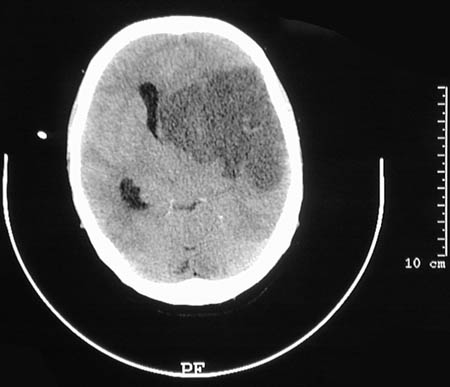

| This CT scan reveals an area of massive infarction of the left cerebral hemisphere, mostly in the right middle cerebral distribution, that is of recent formation, with brain swelling and a midline shift to the right compressing the ventricular system. |